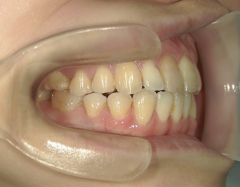

no.37_7548_治療前_右.JPGno.37_7548_治療前_正面.JPGno.37_7548_治療前_左.JPG

no.37_7548_治療後_右.JPGno.37_7548_治療後_正面.JPGno.37_7548_治療後_左.JPG